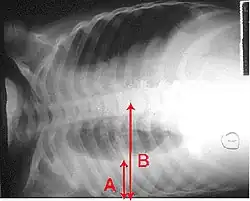

X-ray presentations of pneumonia may be classified as lobar pneumonia, bronchopneumonia, lobular pneumonia, and interstitial pneumonia.[75] Bacterial, community-acquired pneumonia classically show lung consolidation of one lung segmental lobe, which is known as lobar pneumonia.[42] However, findings may vary, and other patterns are common in other types of pneumonia.[42] Aspiration pneumonia may present with bilateral opacities primarily in the bases of the lungs and on the right side.[42] Radiographs of viral pneumonia may appear normal, appear hyper-inflated, have bilateral patchy areas, or present similar to bacterial pneumonia with lobar consolidation.[42] Radiologic findings may not be present in the early stages of the disease, especially in the presence of dehydration, or may be difficult to interpret in the obese or those with a history of lung disease.[24] Complications such as pleural effusion may also be found on chest radiographs. Laterolateral chest radiographs can increase the diagnostic accuracy of lung consolidation and pleural effusion.[41]

A CT scan can give additional information in indeterminate cases[42] and provide more details in those with an unclear chest radiograph (for example occult pneumonia in chronic obstructive pulmonary disease). They can be used to exclude pulmonary embolism and fungal pneumonia, and detect lung abscesses in those who are not responding to treatments.[41] However, CT scans are more expensive, have a higher dose of radiation, and cannot be done at bedside.[41]